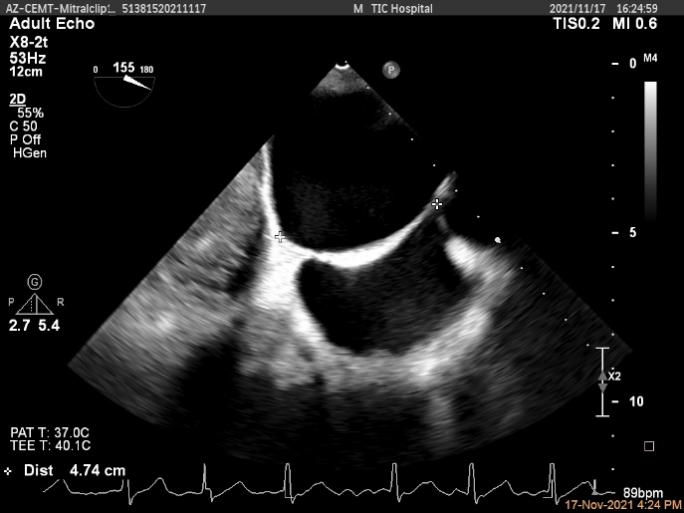

确定房间隔穿刺点

2D视图观察夹子经过大鞘进入左房内